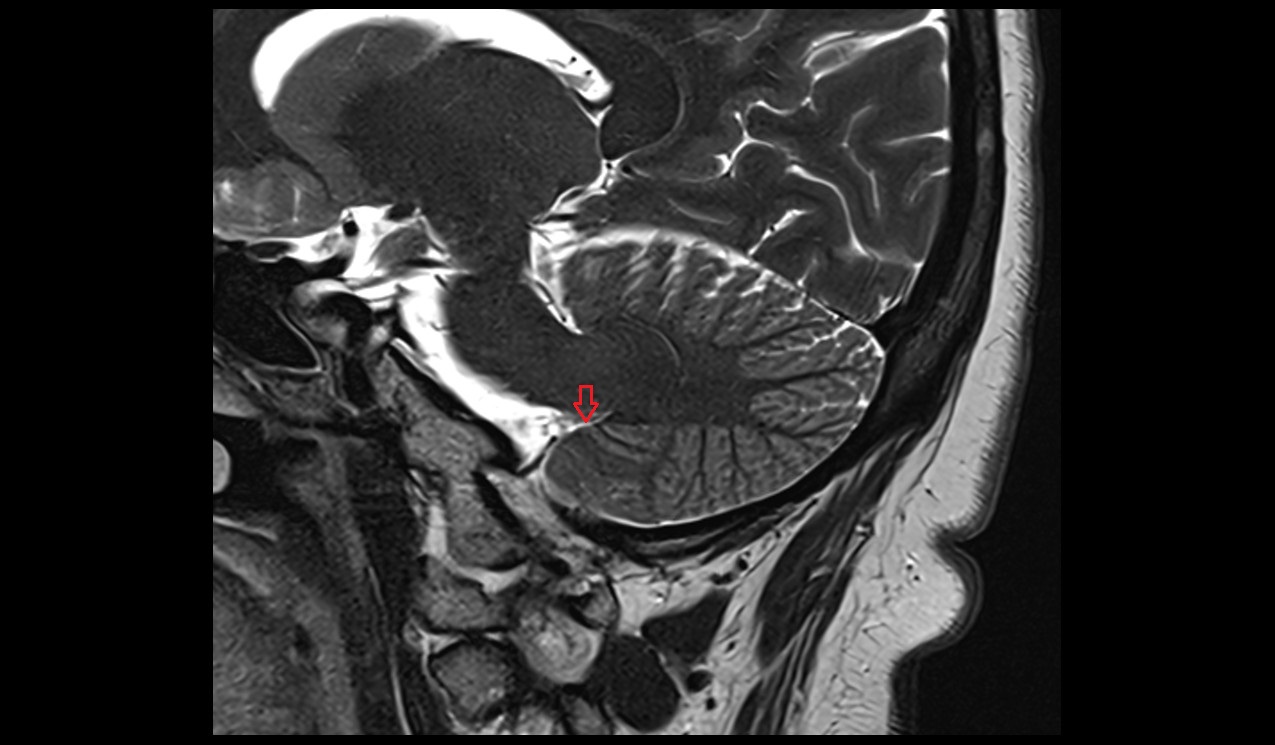

- Median aperture of fourth ventricle (foramen of Magendie)